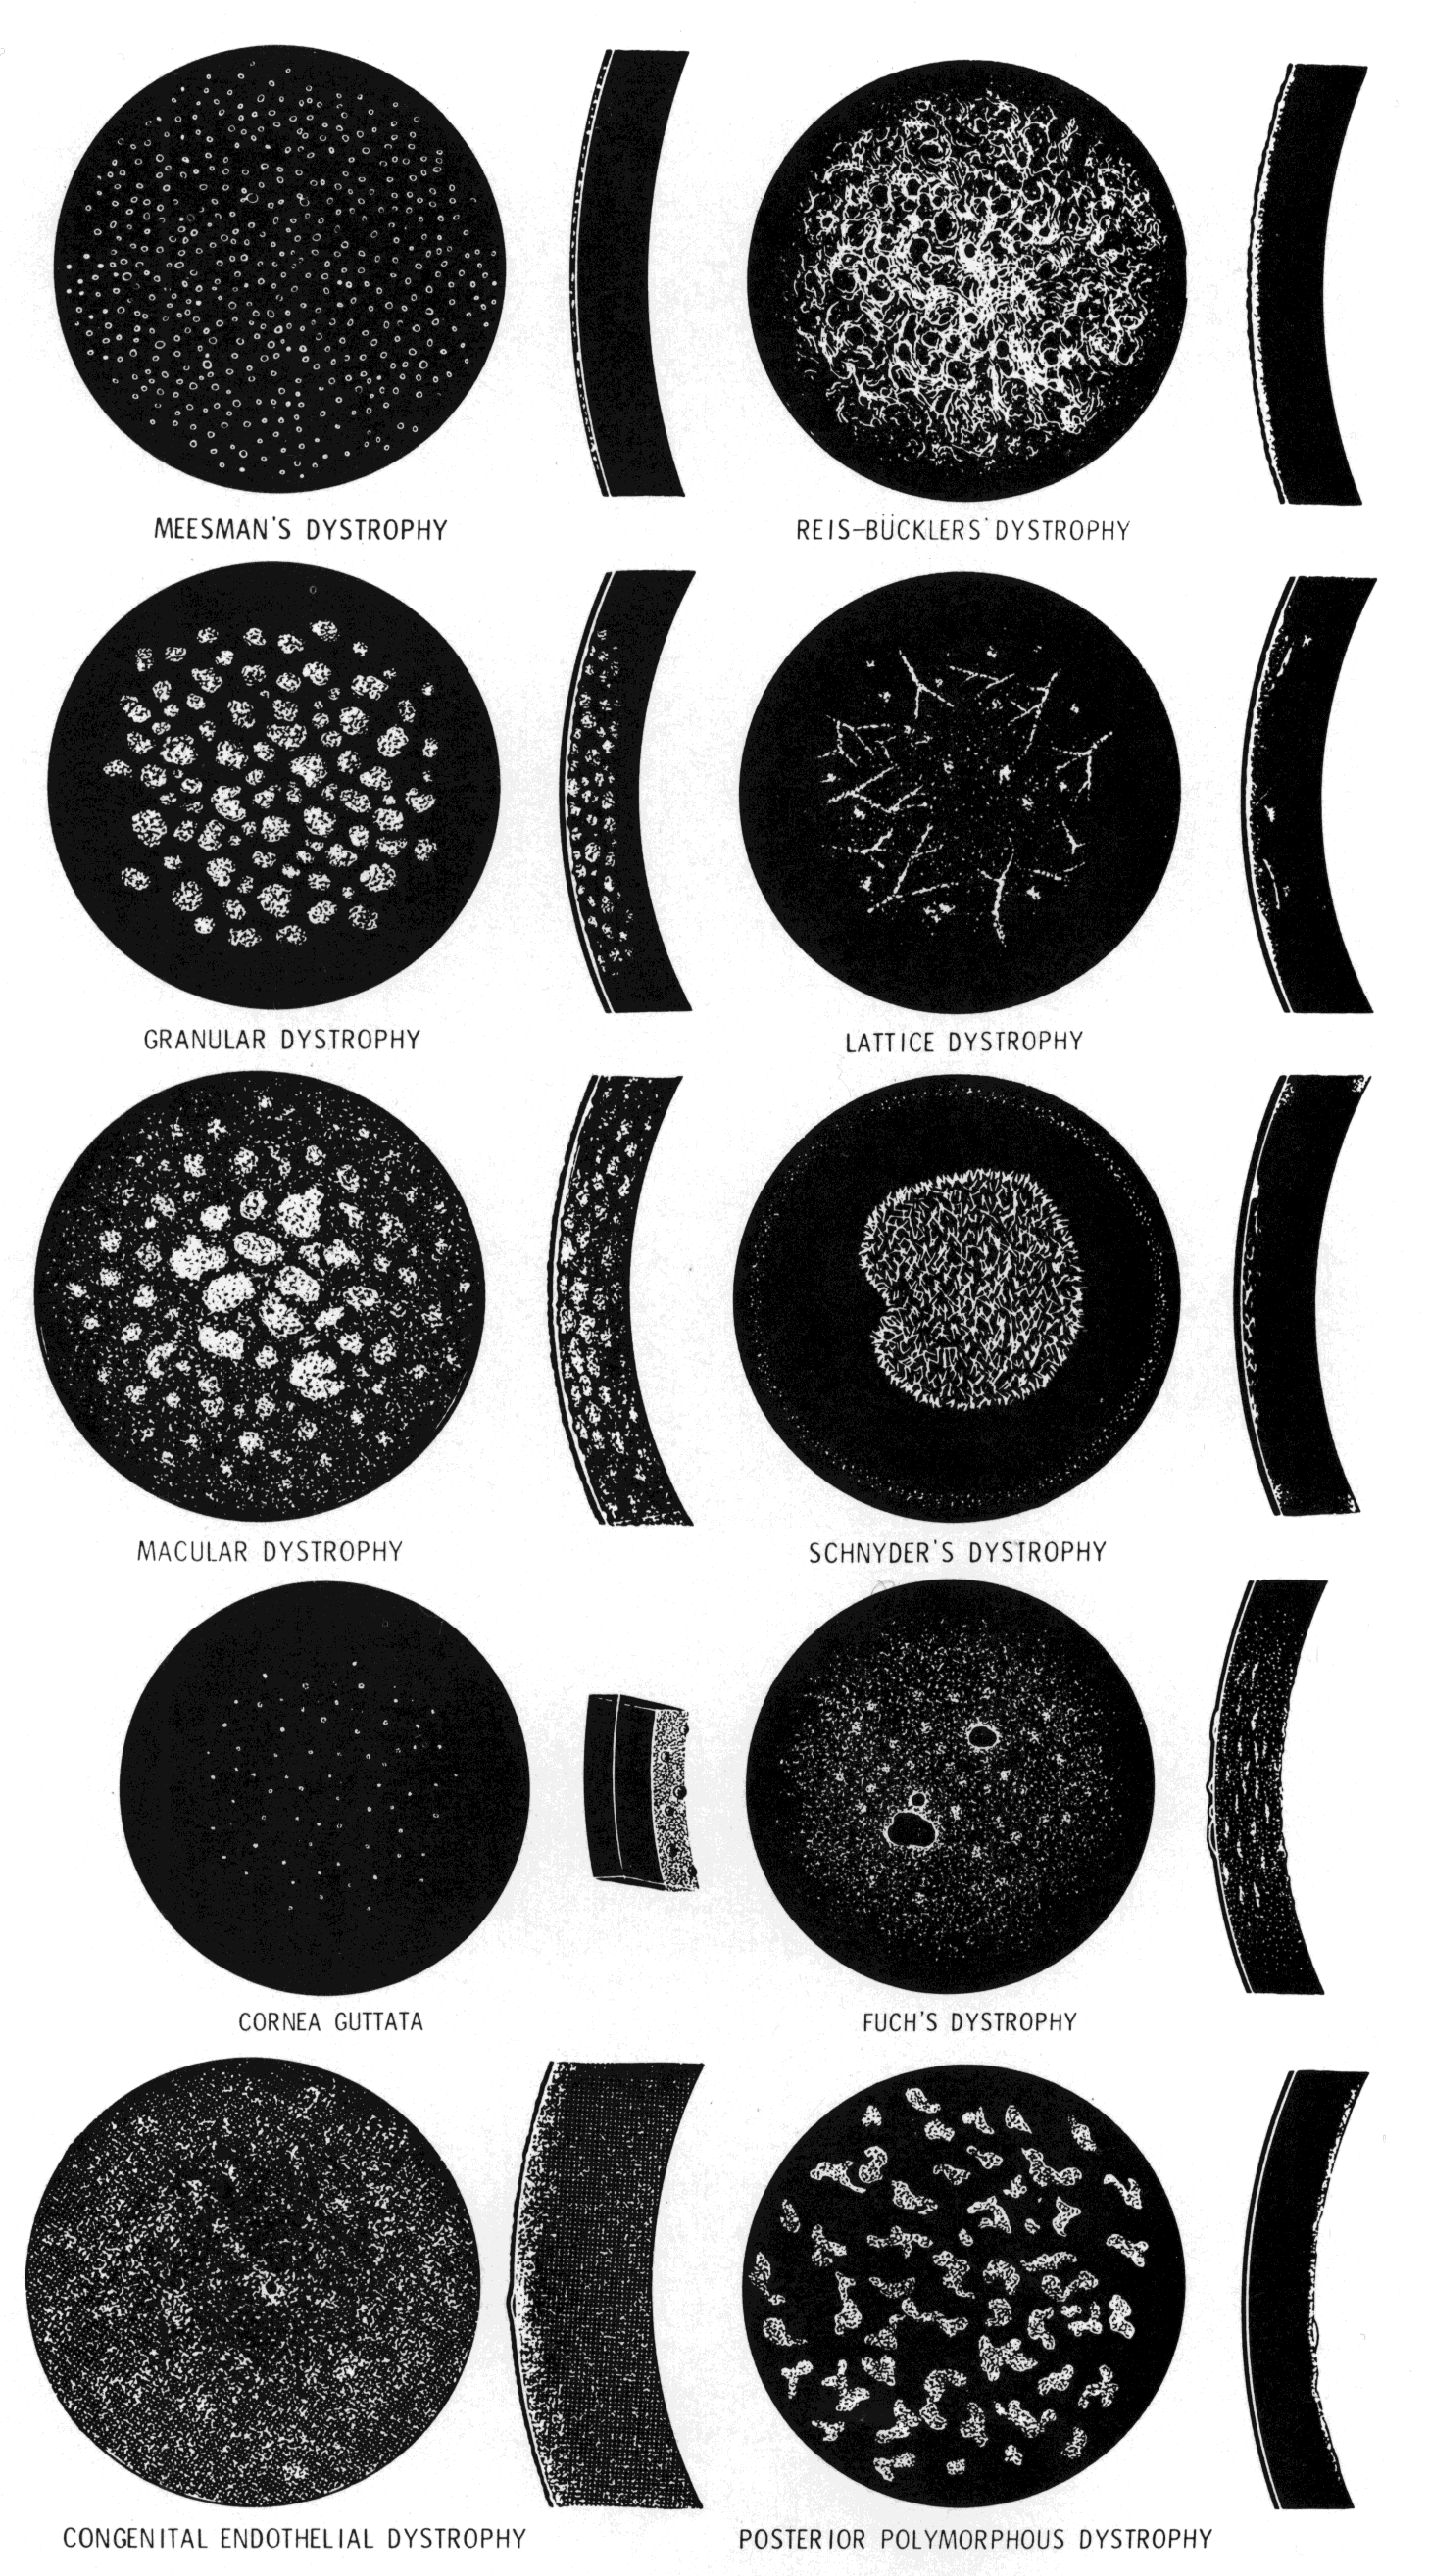

Macular Dystrophy (Groenouw Type II)

Among the classic corneal dystrophies, macular dystrophy, unlike granular and lattice dystrophies, is an autosomal recessive disorder and is far less common. It usually begins in the first decade of life and leads to progressive visual deterioration as the stroma becomes generally cloudy, with superimposed dense, gray-white spots (Figs. 5 AND 11; Color Plate 1H). Unlike granular dystrophy, these macular spots have indefinite edges and the intervening stroma is not clear. Young patients exhibit axial lesions in the superficial layers of the cornea, but with time, lesions approach the periphery and extend throughout the entire stromal thickness. Corneal thinning confirmed by central pachymetry has been documented.129 Also unique is primary involvement of the endothelium as evidenced clinically by the presence of guttate changes of Descemet's membrane.

Fig. 11. Macular corneal dystrophy. Top left. Clinical appearance of cornea features diffuse haze extending to the limbus with superimposed, dense gray-white spots. Bottom left. Light photomicrograph of posterior cornea shows endothelial cells staining intensely positive for acid mucopolysaccharide. Guttate excrescences (*) of Descemet's membrane (DM) are frequent. The stroma also shows positive staining for acid mucopolysaccharide both diffusely extracellularly and intensely within keratocytes (circled) (colloidal iron × 500). Right. Transmission electron micrograph discloses typical fibrillary granular deposits within keratocytes (K), throughout the posterior layer of Descemet's membrane, and within the endothelial cells (En). The anterior banded region of Descemet's membrane (bracketed) is not affected (× 3500).

The lesions in macular corneal dystrophy stain intensely with alcian blue and colloidal iron, minimally with PAS, and not at all with Masson's trichrome. Birefringence is decreased. The lesions have been histochemically identified as an abnormal keratan sulfate-like glycosaminoglycan that accumulates extracellularly within the stroma and Descemet's membrane and intracellularly within keratocytes and endothelium.130

As would be typical of an autosomal recessively inherited condition, macular dystrophy presumably results from deficiency of a hydrolytic enzymes (sulfotransferase) and may thus be considered a localized mucopolysaccharidosis.131 The effect of altered glycosaminoglycan metabolism is evident at the cellular level; on transmission electron microscopy, keratocytes and endothelial cells exhibit distention of rough-surfaced endoplasmic reticulum cisternae. With the acridine orange technique, compensatory generalized hyperactivity of the lysosomal enzyme system has been demonstrated.132 Eventually the accumulated undigested storage products engorge the cells, and the cells ultimately degenerate or rupture. The derivation of these intracytoplasmic storage vacuoles from endoplasmic reticulum suggests that the biochemical lesion in macular dystrophy occurs at a different metabolic location than in the systemic mucopolysaccharidoses, since in the latter, storage products accumulate within lysosomelike intracytoplasmic vacuoles associated with the Golgi complex.133 Snip and associates134 were able to determine that the storage phenomenon affecting endothelium and Descemet's membrane is likely also primary, since the intracellular and extracellular lesions appear ultrastructurally comparable to those evident in the keratocytes and stroma.

Two subtypes of macular dystrophy have been immunohistochemically identified. Type I is most prevalent and is characterized by the absence of antigenic keratan sulfate in the cornea as well as in the serum; it, in fact, may represent a more widespread systemic disorder of keratan sulfate metabolism.135 In type 2, antigenic keratan sulfate is present in both cornea and serum.

The treatment for macular dystrophy is corneal transplantation. Recurrence in the graft has been reported.119,136